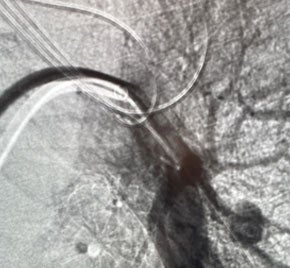

Hemoptysis treated with Embold Fibered​ Coils

Scan of vein before placement of coil. Visualizing the pulmonary artery​

Scan of vein after Embold fibered coil. After Embold Fibered placement​

Keshav Anand, MD

University of Utah

Salt Lake City, UT